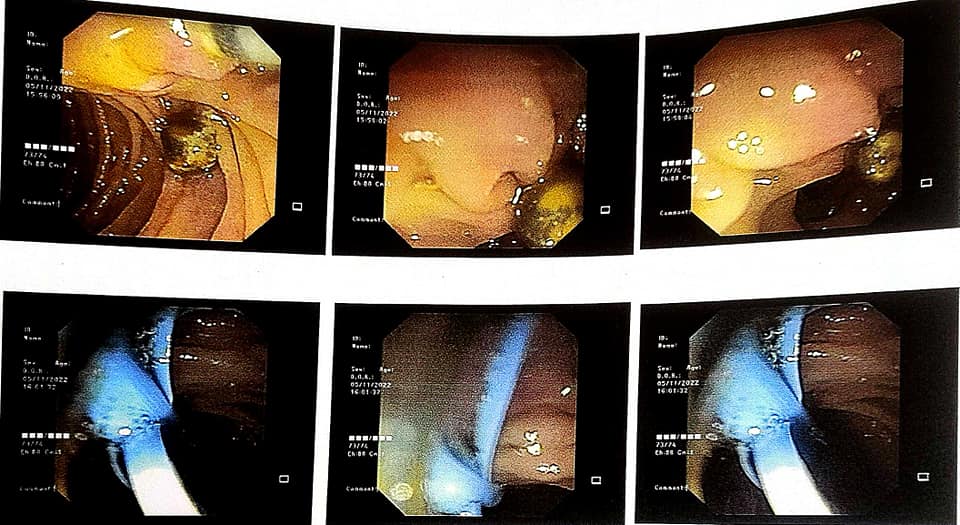

Successful Management of Acute Pancreatitis with Choledocholithiasis

A 55-year-old male presented to the emergency room with sudden and severe abdominal pain, subsequently diagnosed as acute pancreatitis. The patient was managed conservatively in the critical care unit. On the first day, he developed fever, and liver function tests (LFTs) indicated a cholestatic pattern. Aggressive treatment commenced, including higher antibiotics and ursodeoxycholic acid (UDCA). However, minimal improvement was observed in LFTs on the second day. Further investigations revealed choledocholithiasis with gallbladder calculi on magnetic resonance cholangiopancreatography (MRCP). Inflammatory markers such as C-reactive protein (CRP) and procalcitonin were significantly elevated. Urgent endoscopic retrograde cholangiopancreatography (ERCP) with stone removal and biliary stent deployment was performed, leading to a smooth recovery.

The patient was discharged on the seventh day with normalized LFTs and infection markers. In a subsequent interval laparoscopic cholecystectomy performed the following month, the procedure proceeded without complications. The biliary stent was removed, and clearance of the common bile duct (CBD) was confirmed on repeat ERCP. This case highlights the effectiveness of urgent ERCP and stenting in preventing major complications associated with choledocholithiasis. Additionally, the timely intervention reduced hospital stay and mitigated the risk of sepsis, underscoring the importance of prompt diagnosis and management in acute pancreatitis with concurrent biliary tract obstruction.